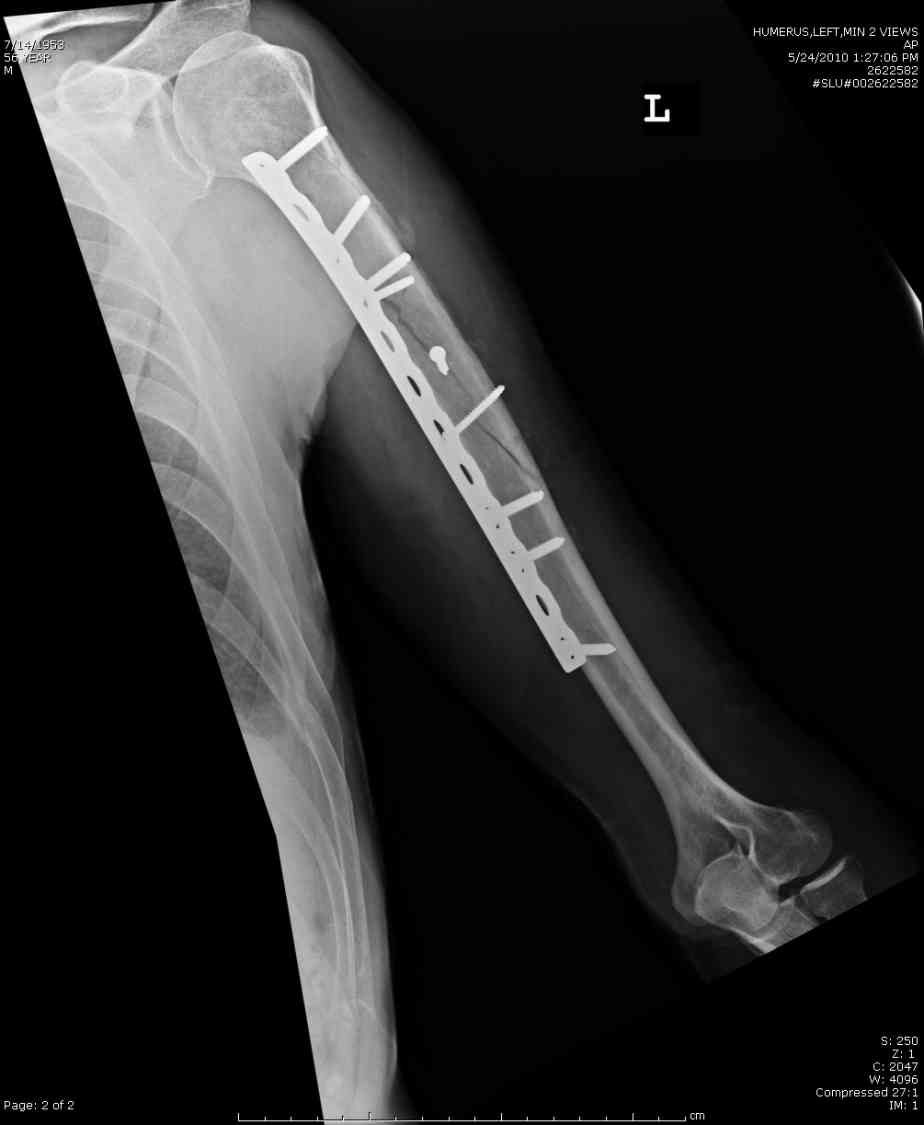

Добрый вечер!

Приложение как пример.

Что иллюстрирует этот пример? Это была множественная травма? Если это был изолированный перелом, то "золотой стандарт" - консервативное лечение.

Консервативно он уже лечился до этой операции в течение трёх с половиной месяцев.

А именно такой вариант операции выбран из экономических соображений.

вообще, торчашие в субакромиальное пространство шипы оставляют неизгладимое впечатление. Не думаю, что таким имплантом есть смысл гордиться

Кроме интрамедуллярного остеосинтеза, имеются другие варианты фиксации, наружный фиксатор и например здесь перелом плеча с повреждением нерва леченный открытым методом. Применен задний доступ с инспекцией нерва, межфрагментарная компрессия, фиксация узкой пластиной 4.5 мм.